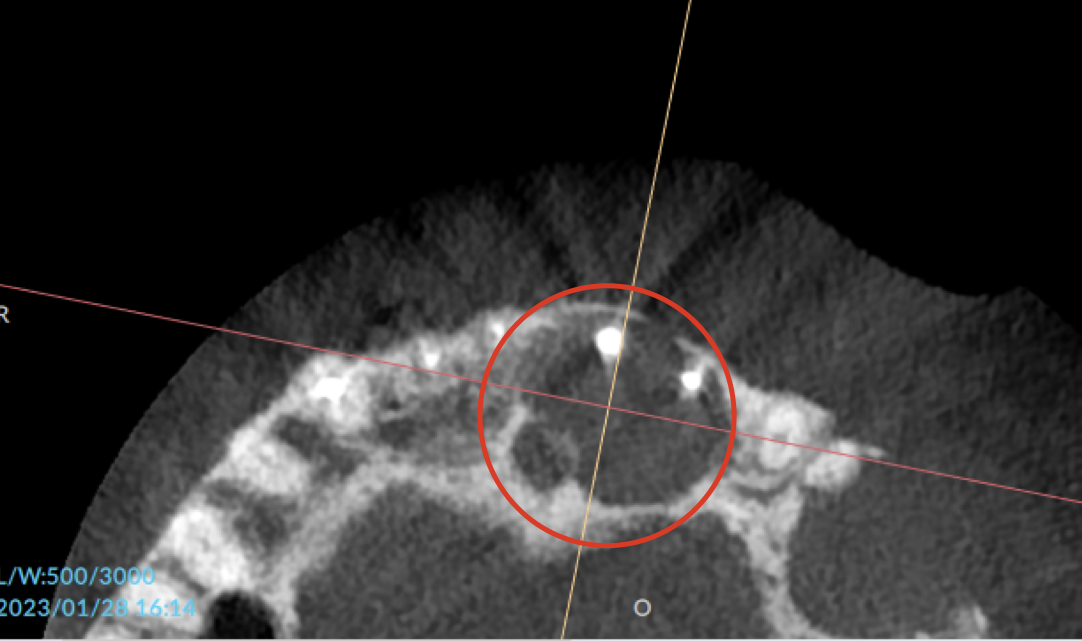

レントゲン・CTで撮影すると、上顎の前歯はかなり厳しい状態でした。

誰が見ても骨の喪失が明らかなほどで、抜歯は免れないレベルでした。

CT①